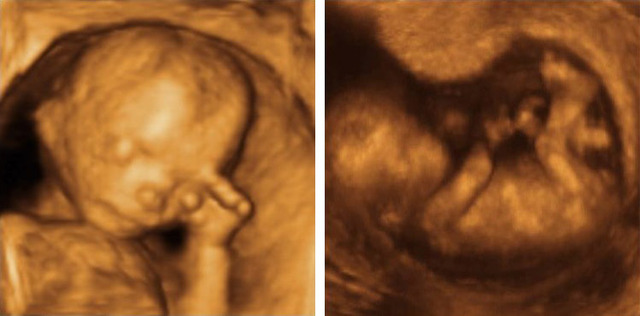

• week 16

week 16

Get ready for a growth spurt. In the next few weeks, your baby will double his weight and add inches to his length. Right now, he's about the size of an avocado: 4 1/2 inches long (head to rump) and 3 1/2 ounces. His legs are much more developed, his head is more erect than it has been, and his eyes have moved closer to the front of his head.